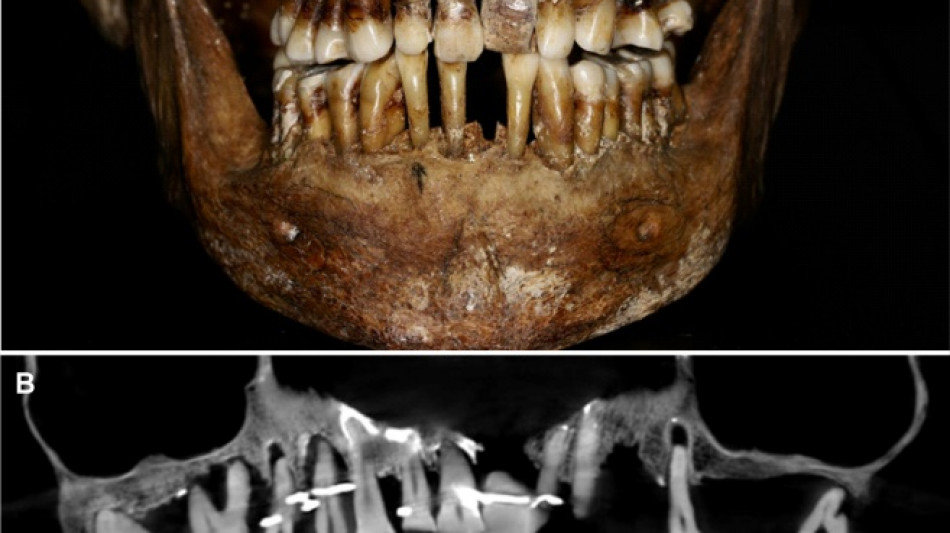

Embalmed in a lead coffin, her skeleton -- and teeth -- were remarkably well preserved.

At the time the archaeologists noticed that she had a dental prosthetic, but they did not have advanced scanning tools to find out more.

Thirty-five years later, a team of archaeologists and dentists have identified that d'Alegre suffered from periodontal disease that was loosening her teeth, according to a study published in the Journal of Archaeological Science: Reports this week.

A "Cone Beam" scan, which uses X-rays to build three-dimensional images, showed that gold wire had been used to hold together and tighten several of her teeth.

She also had an artificial tooth made of ivory from an elephant -- not hippopotamus, which was popular at the time.